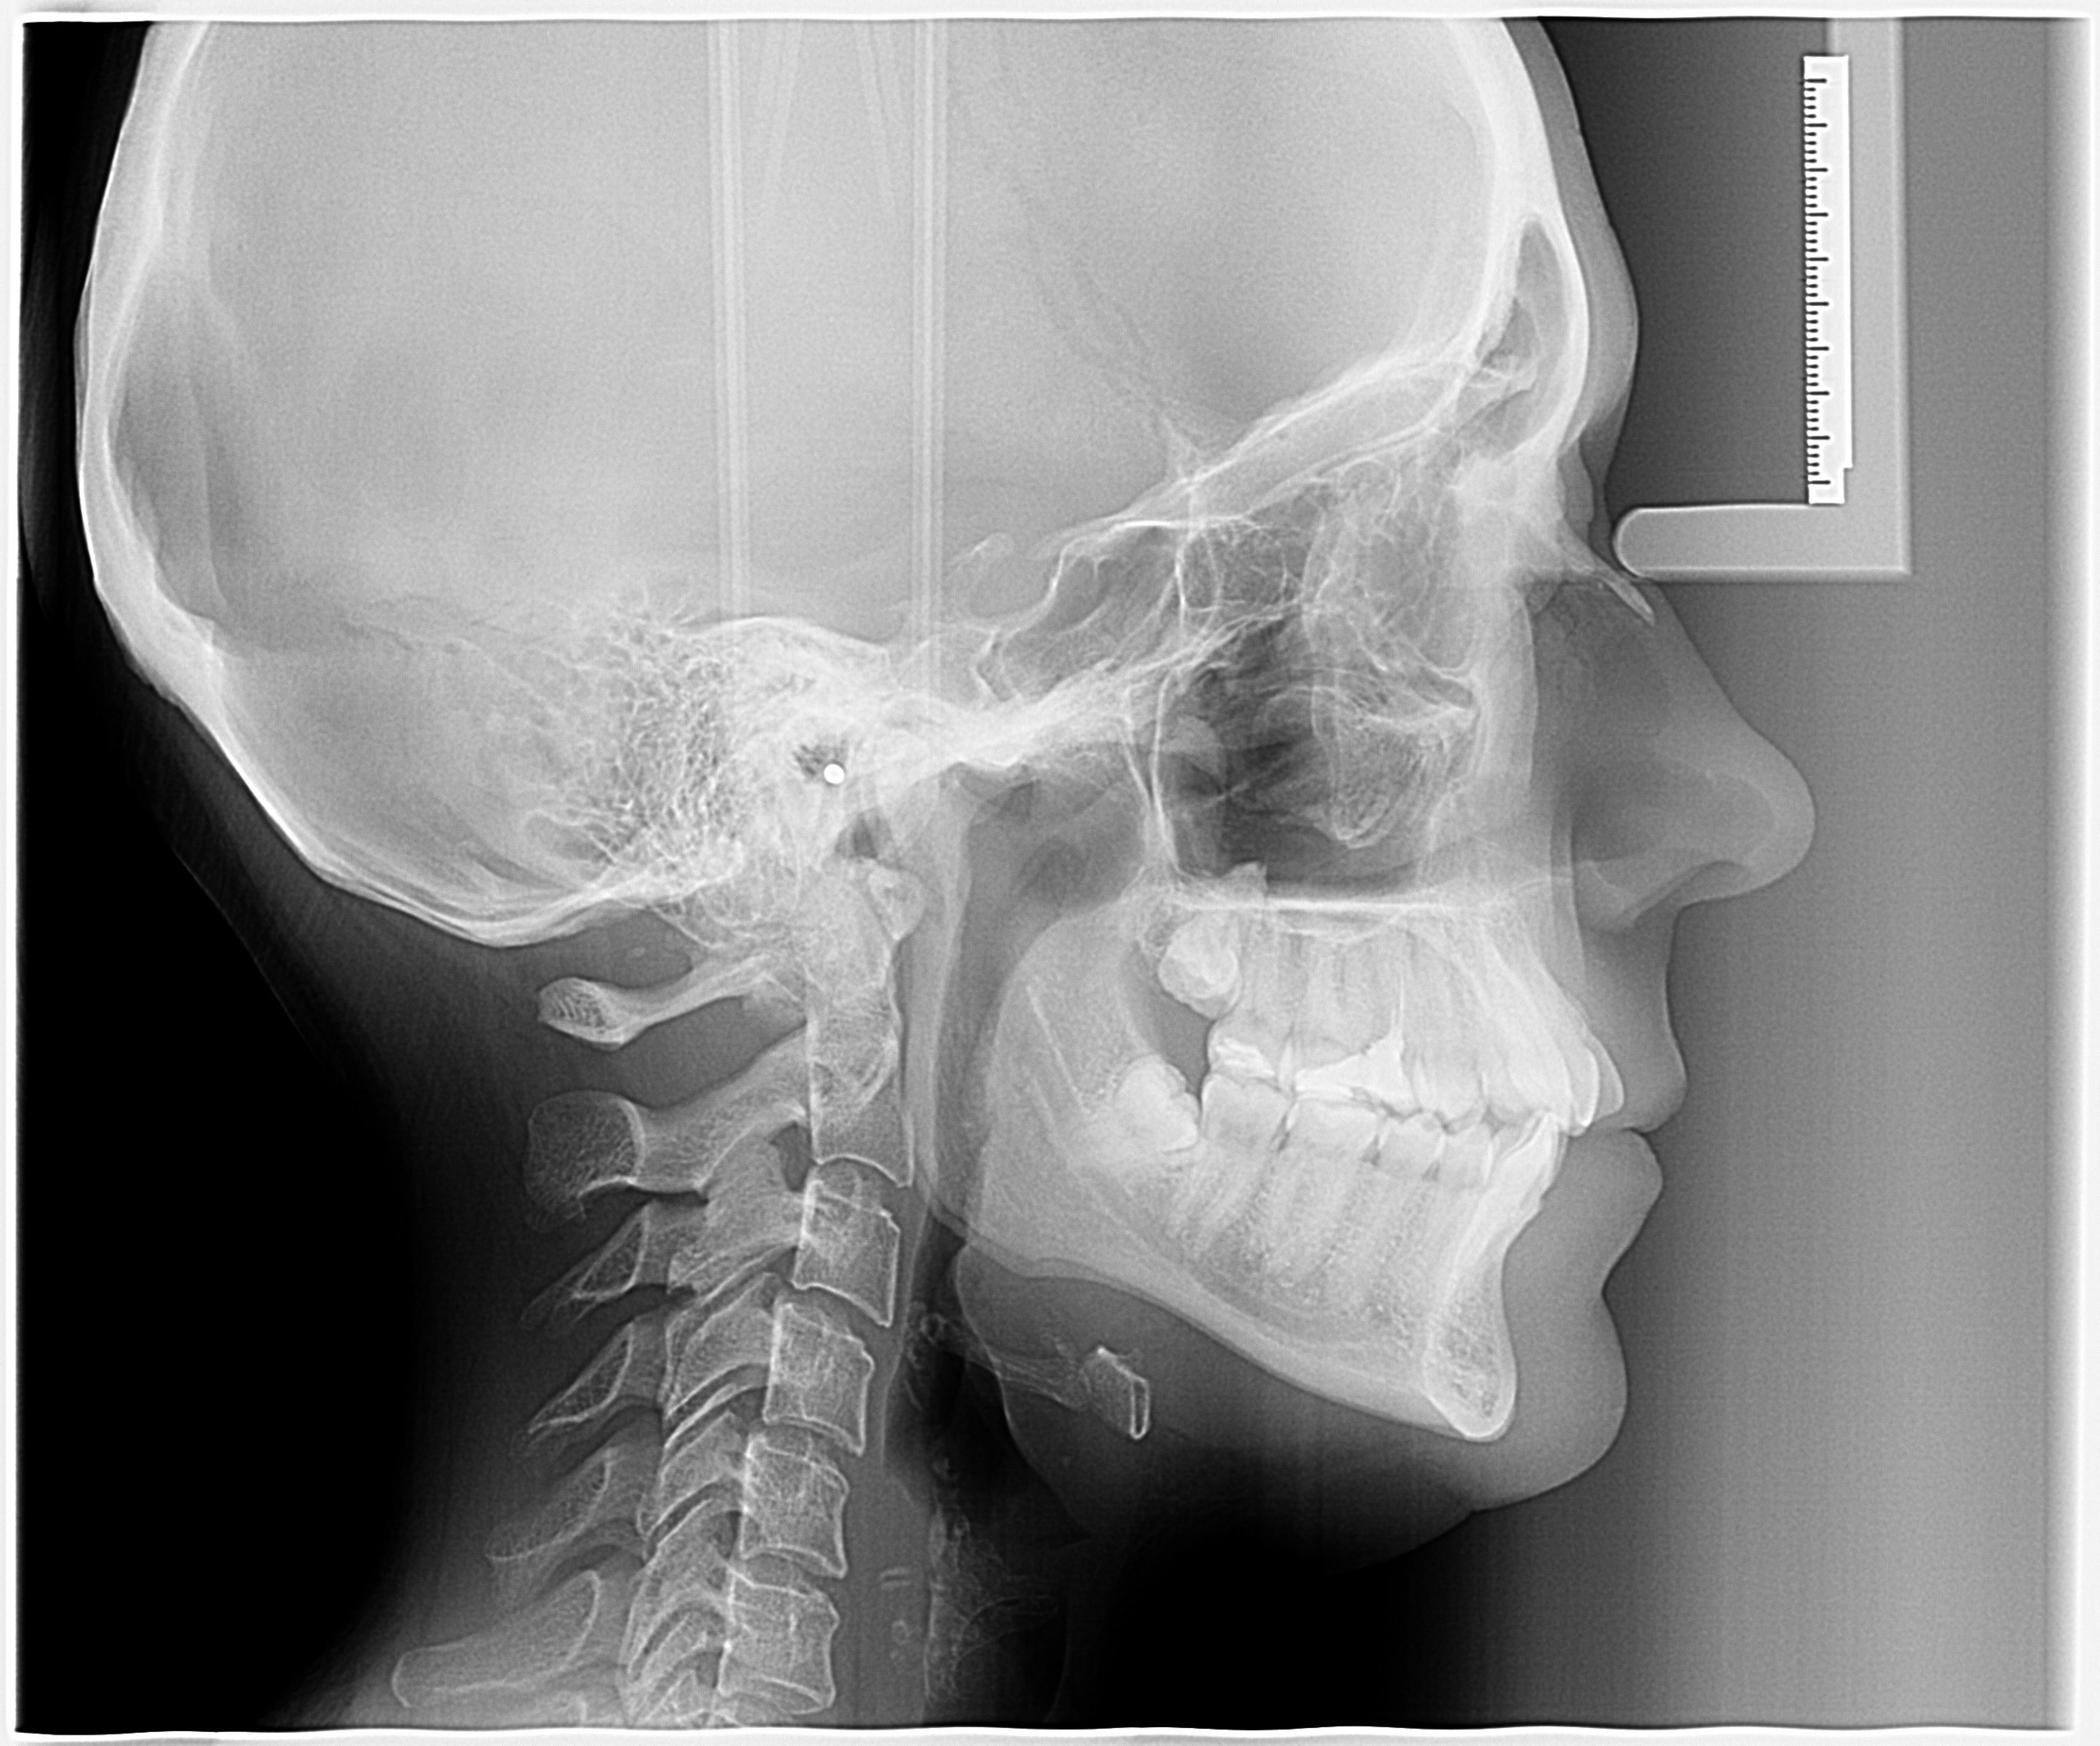

Телерентгенограмма в боковой проекции (ТРГ)